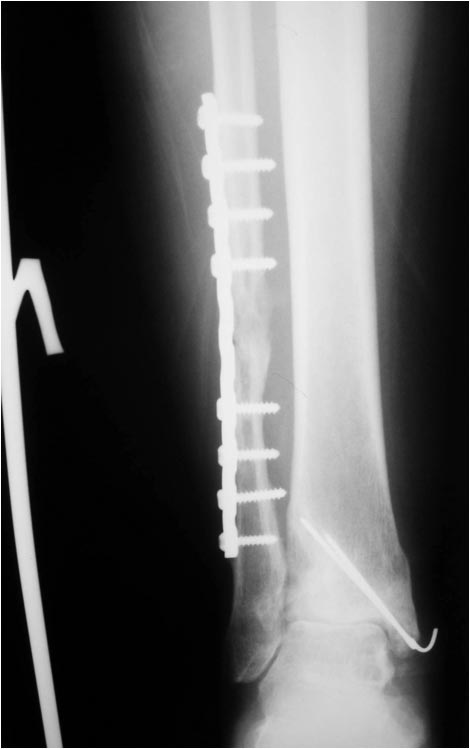

Оперировал эту пациентку 23 лет 11 лет назад через 8 месяцев после

похожего на представленный Вами остеосинтез. На первой операции перелом

малоберцовой кости в нижней трети был просто не замечен. За счет

восстановления оси быстро развившийся артроз протекал благоприятно. В

результате артродез был выполнен только в прошлом году, через 10 лет

после второй операции. И боли беспокоили пациентку только в течение года

перед артродезом.